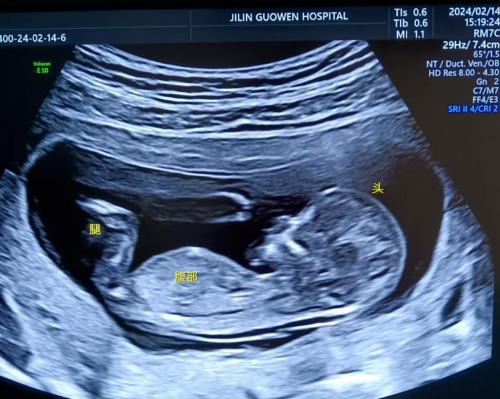

超聲檢查,孕婦無需空腹。檢查時(shí),超聲醫(yī)生會(huì)使用超聲儀器對(duì)胎兒頸部進(jìn)行仔細(xì)觀察和測量。通過超聲探頭可以清晰地看到胎兒在子宮內(nèi)的情況,重點(diǎn)測量胎兒頸項(xiàng)部皮下無回聲透明層最厚的部位,測量值即為 NT 值。正常胎兒 NT 值一般不超過 2.5mm。